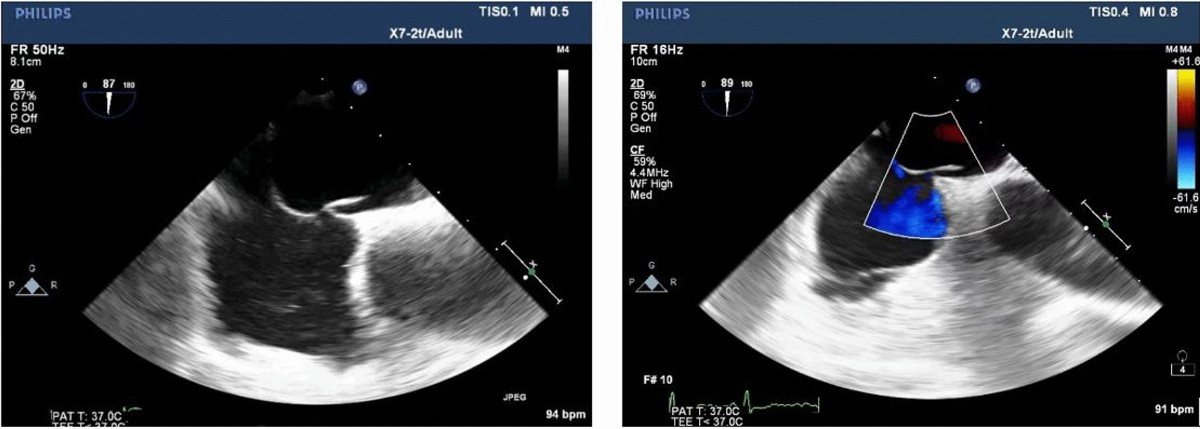

pfo echocardiography sale